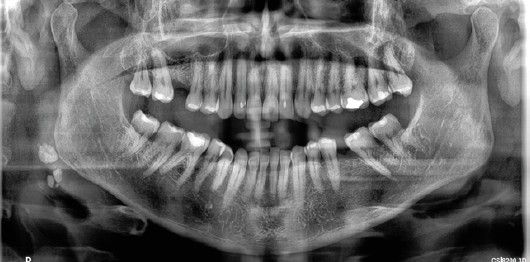

La radiografía panorámica es una de las pruebas diagnósticas más utilizada en la práctica clínica dental. Nos ofrece mucha información sobre las estructuras orales y faciales, así como sobre el área de las primeras vértebras cervicales. En este sentido, Friedlander y Lande señalaron en 1981, la gran oportunidad que tienen los dentistas de contribuir a la detección precoz de las calcificaciones carotídeas de sus pacientes, factores indicativos de alto riesgo de accidente cerebrovascular, simplemente prestando atención a las ortopantomografías bucales que les realizan con regularidad7.

Los estudios disponibles coinciden en que las imágenes compatibles con calcificaciones carotídeas observadas en una ortopantomografía, ubicadas entre la 2ª-3ª-4ª vértebras, suelen ser posteriormente confirmadas como ateromas carotídeos mediante la técnica eco-Doppler7-12.

Estas calcificaciones que, generalmente se localizan en la bifurcación carotídea, se presentan como masas radiopacas en la región de la radiografía panorámica correspondiente a los tejidos blandos del cuello, en una zona aproximada entre las vértebras cervicales C2, C3 y C4, a una distancia aproximada entre 1 y 4 cm posteroinferior al ángulo mandibular13. Pueden variar en tamaño y forma, siendo lineales verticales, nodulares o heterogéneas, y pueden presentarse de manera unilateral o bilateral, así como ser únicas o múltiples13-15.

El objetivo de esta publicación es contribuir a la prevención de los problemas cerebrovasculares desde la clínica dental, mediante la presentación de tres casos clínicos en los que se detectaron de manera casual calcificaciones carotídeas durante un examen radiográfico de control, realizado mediante una radiografía panorámica, en pacientes con patologías periodontales en fase de mantenimiento.